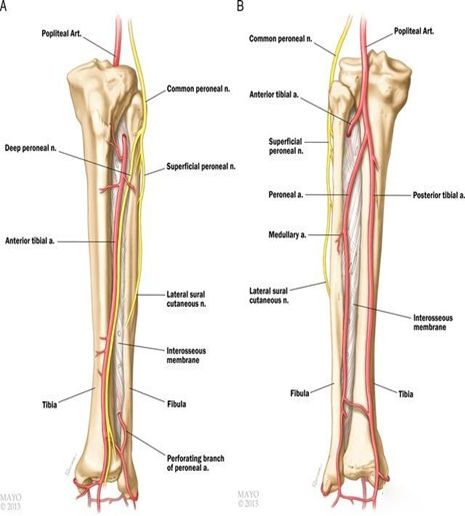

1、胫骨略向外弯,有12-15度生理弧度,骨干的上2/3呈三棱形,下1/3逐渐变为四方形,中下1/3交界处相对较细,是骨折的好发部位。

2、胫骨前内侧无肌肉附着,仅被皮肤覆盖,骨折移位大者,易刺破皮肤,造成开放性损伤。

3、胫骨上1/3后方有腘动脉及其分支胫前动脉、胫后动脉通过;腓骨小头的内下方有腓总神经通过,该部位骨折,有可能损伤血管和神经。

4、胫骨的滋养动脉于上1/3后方进入骨皮质下行,支配中、下段血供,因此胫骨中下段骨折,血供破坏,可发生迟缓愈合或不愈合。